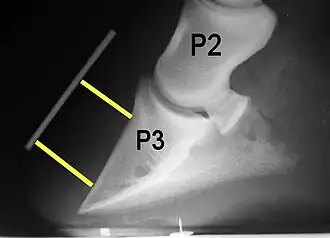

Rotation is the most common form of displacement, and, in this case, the tip of the coffin bone rotates downward.[4] The degree of rotation may be influenced by the severity of the initial attack and the time of initiation and aggressiveness of treatment. A combination of forces (e.g. the tension of the deep digital flexor tendon and the weight of the horse) result in the deep digital flexor tendon literally pulling the dorsal face of the coffin bone away from the inside of the hoof wall, which allows the coffin bone to rotate. Also, ligaments attaching the collateral cartilages to the digit, primarily in the palmar portion of the foot, possibly contribute to a difference in support from front to back. The body weight of the animal probably contributes to rotation of the coffin bone. Rotation results in an obvious misalignment between PII (the short pastern bone) and PIII (the coffin bone). If rotation of the third phalanx continues, its tip can eventually penetrate the sole of the foot.

Radiographs are an important part of evaluating the laminitic horse. They not only allow the practitioner to determine the severity of the episode, which does not always correlate with degree of pain,[1] but also to gauge improvement and response to treatment. Several measurements are made to predict severity. Additionally, radiographs also allow the visualization and evaluation of the hoof capsule, and can help detect the presence of a lamellar wedge or seromas.[1] The lateral view provides the majority of the information regarding degree of rotation, sole depth, dorsal hoof wall thickness, and vertical deviation.[1][17] A 65-degree dorsopalmar view is useful in the case of chronic laminitis to evaluate the rim of the coffin bone for pathology.[1]

Several radiographic measurements, made on the lateral view, allow for objective evaluation of the episode.

- Palmar angle (PA): the angle between a line perpendicular to the ground, and a line at the angle of the palmar surface of P3.

- Horn:lamellar distance (HL): the measurement from the most superficial aspect of the dorsal hoof wall to the face of P3. 2 distances are compared: a proximal measurement made just distal to the extensor process of P3, and a distal measurement made toward the tip of P3. These two values should be similar. In cases of rotation, the distal measurement will be higher than the proximal. In cases of distal displacement, both values will increase, but may remain equal. Therefore, it is ideal to have baseline radiographs for horses, especially for those at high-risk for laminitis, to compare to should laminitis ever be suspected. Normal HL values vary by breed and age:[1]